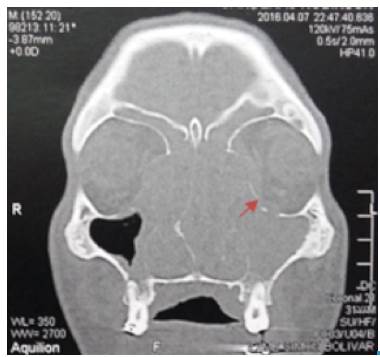

Blood tests were negative for human immunodeficiency virus (HIV), venereal disease research laboratory (VDRL) and hepatitis B and C, and C-reactive protein test (CRP) was less than 10 mg/L. Computed tomography scan in face and neck showed a mass occupying the nasal cavity, extended to the nasopharynx. The paranasal sinuses were occupied by homogeneous soft tissue density material; left lamina papyracea was eroded and the periorbital fat had inflammatory changes (Figure 2). Lymph nodes of the neck were compromised at zones IIa y IIb. The upper airway was patent. No lesions were identified in CT scans of thorax and abdomen. The patient was hospitalized and multiple punch biopsies of the soft palate were taken.

CT scan of nose and paranasal sinuses. Coronal view: complete occupation of left maxillary sinus, frontal and bilateral ethmoidal sinuses. Arrow: Eroded left lamina papyracea.

Figure 2: CT scan of nose and paranasal sinuses. Coronal view: complete occupation of left maxillary sinus, frontal and bilateral ethmoidal sinuses. Arrow: Eroded left lamina papyracea.